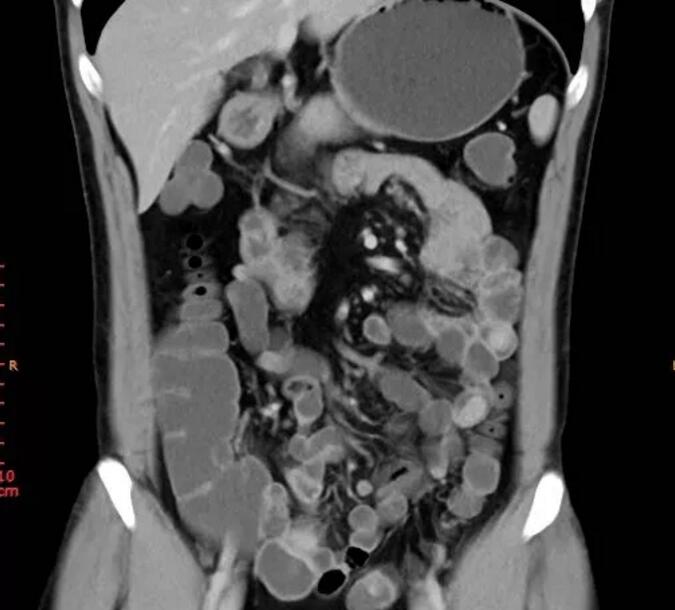

近日,復旦大學附屬中山醫院吳淞醫院就收治了這樣一例罕見的黑斑息肉綜合征,5月12日下午,專家為病患實施了小腸鏡下息肉切除術,經過40分鐘的手術時間,一個5厘米大小的巨大息肉被摘除,術后,患者恢復良好。

與我們常規知曉的腸鏡不同的是,此次手術實施的部位在小腸,位置更深、直徑更細、腸壁更薄,全長有5~7米,小腸鏡的操作難度也更大,目前國內只有少數的醫院和專家才能開展。

據了解,黑斑息肉綜合征,又稱PJ綜合征,是一種家族遺傳性疾病;颊叨嘤锌诖胶诎,既往多有腸梗阻、腸套疊病史及相關手術史,部分患者的父母、兄弟姐妹、子女也有類似表現及手術史。該病發病率很低,僅為1/50000~200000,但癌變風險卻較高,盡快切除是治療的首選方式。但由于息肉會再次生長,而小腸是人體消化吸收最重要的部位,反復多次進行傳統的切除長有息肉的小腸手術,可能導致患者致殘,甚至危及生命。如今,專家運用小腸鏡,通過微創的方式為患者切除息肉,大大降低了患者的手術風險。